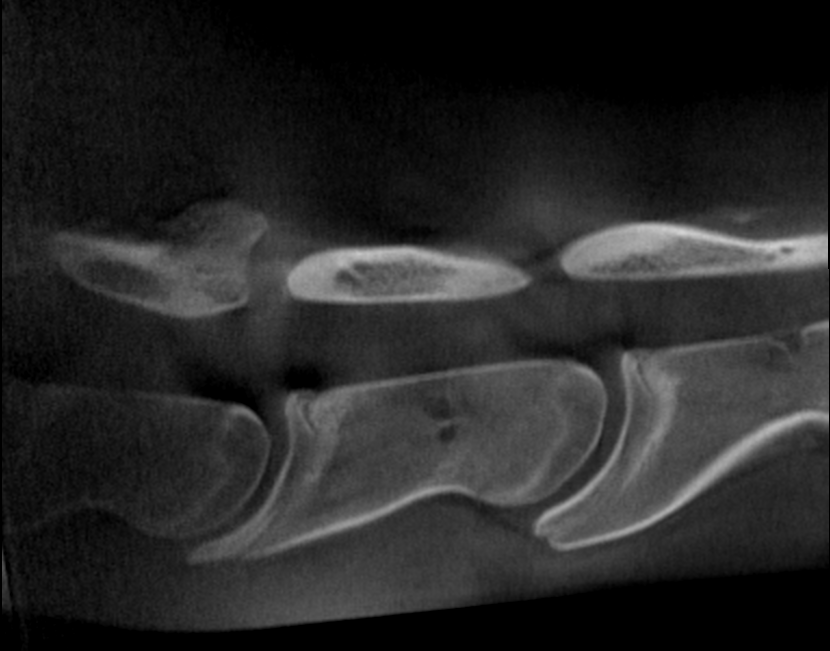

Our High Definition Volumetric Imaging (HDVI) technology represents the most advanced stage of Flat Panel CT technology. It offers exceptional diagnostic imaging for both hard and soft tissues, in diagnostic settings and intraoperative theaters. It is the gold standard for orthopedic applications.

Scan of the standing horse

Pegaso scans head, neck and limbs of the standing horse